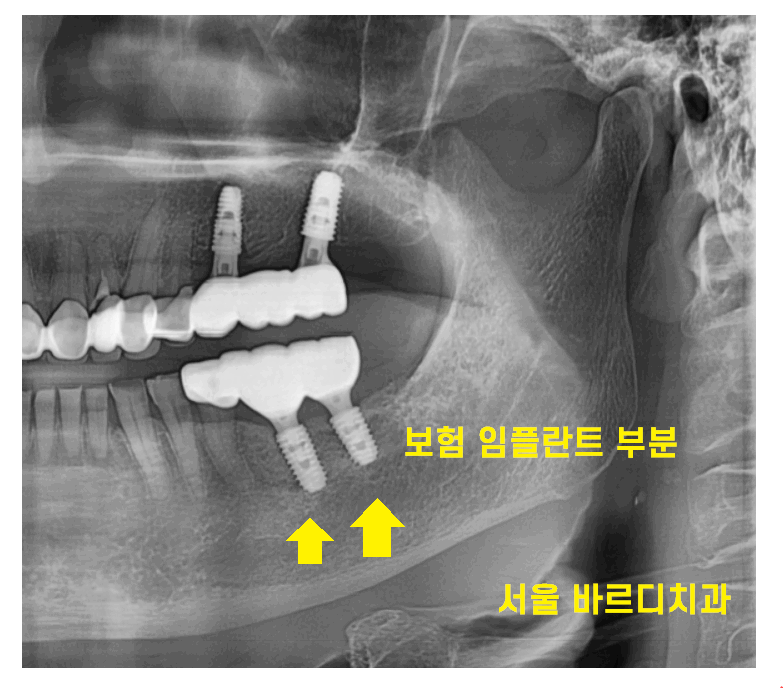

예전에 저희 병원에서 보험 임플란트 수술하신

환자분인데요~

24.02.02

발치 후

보험 임플란트 혜택 적용받으셔서

임플란트 완료하셨습니다.